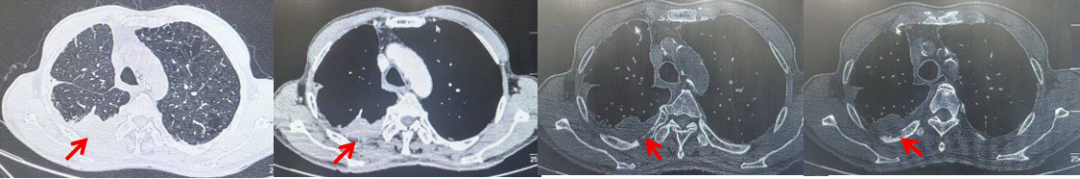

71岁男性,高血压病史20年,口服药物治疗,无糖尿病、心脏病等基础疾病,吸烟史50年,20支/天,已戒1年余,无饮酒史,无肿瘤家族史。2023.11因咳嗽、咳痰行胸CT检查:左肺下叶占位性病变,大小约12mmx8mm(如图5)。2023.11.20行“单孔胸腔镜左肺中下叶切除、肺门及纵隔淋巴结清扫、胸膜粘连松解术”;术后病理:(左肺下叶)结合免疫组化鳞状细胞癌(中、低分化),局部见脉管内癌栓,未见确切神经侵犯,(气管切缘)净。(淋巴结)未见转移癌0/19(4组0/1;5组0/1;6组0/2;7组0/1;9组0/1;10组0/2;11组0/3;12组0/2;13组0/2;14组0/4)。术后分期pT1bN0M0 IA期,术后定期复查。

2024.09.12复查胸部CT示左侧胸膜结节,大者约为27mmx13mm,考虑转移可能性大,纵隔淋巴结增大,恶性?(如图6)。患者行胸膜穿刺活检取病理,结果示(胸膜)结合免疫组化,支持鳞状细胞癌,PD-L1(克隆号28-8)TPS约20%。分期为rT0N2bM1a IVA期,DFS为10个月。2024.09.24起行替雷利珠单抗联合紫杉醇+卡铂方案治疗4周期,复查胸CT评效SD(如图7)。后患者因脑梗塞停止治疗,于综合医院就诊,后未返院复查及治疗。

图5:患者手术前(2023.11)胸部CT肺窗及纵隔窗

图6:患者胸膜及纵隔转移(2024.09)胸部CT肺窗及纵隔窗